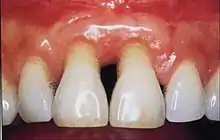

Gingivitis is a common condition that affects the gingiva or mucosal tissues that surround the teeth. The condition is a form of periodontal disease; however, it is the least devastating, in that it does not involve irreversible damage or changes to the periodontium (gingiva, periodontal ligament, cementum or alveolar bone). It is commonly detected by patients when gingival bleeding occurs spontaneously during brushing or eating. It is also characterised by generalised inflammation, swelling, and redness of the mucosal tissues. Gingivitis is typically painless and is most commonly a result of plaque biofilm accumulation, in association with reduced or poor oral hygiene. Other factors may increase a person's risk of gingivitis, including but not limited to systemic conditions such as uncontrolled diabetes mellitus and some medications. The signs and symptoms of gingivitis can be reversed through improved oral hygiene measures and increase plaque disruption. If left untreated, gingivitis has the potential to progress to periodontitis and other related diseases that are more detrimental to periodontal and general health.[9]

Healthy gingiva can be described as stippled, pale or coral pink in Caucasian people, with various degrees of pigmentation in other races. The gingival margin is located at the cemento-enamel junction without the presence of pathology. The gingival pocket between the tooth and the gingival should be no deeper than 1-3mm to be considered healthy. There is also the absence of bleeding on gentle probing.[10]